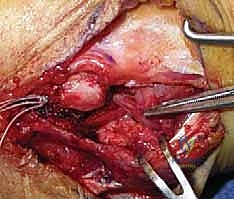

بالنسبة للغالبية العظمى من المرضى النشطين، والشباب، والرياضيين، تعتبر الجراحة هي الحل الجذري والوحيد لاستعادة استقرار الكوع ومنع التآكل الغضروفي المبكر (الخشونة). نظراً لأن الأربطة الممزقة بشكل مزمن تضمر وتفقد جودتها، فإن مجرد خياطتها (الإصلاح المباشر) غالباً ما يبوء بالفشل. لذلك، فإن الإجراء المفضل عالمياً والذي يبرع فيه الأستاذ الدكتور محمد هطيف هو إعادة بناء الرباط (Reconstruction) باستخدام رقعة وترية.